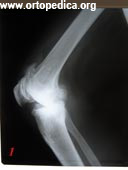

1. Больной Д. рентгенограмма левого коленного сустава в боковой проекции. Диагноз - артроз левого коленного сустава 3 ст.